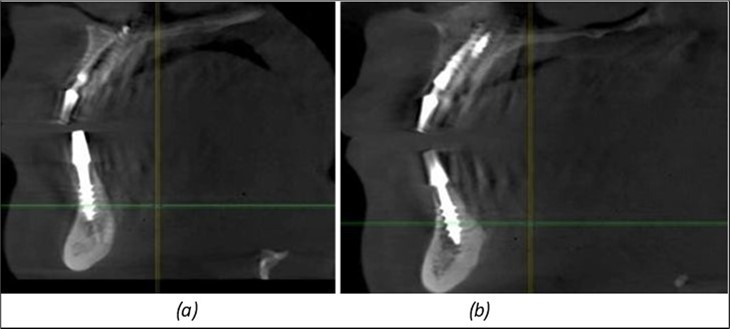

Figure 11.Implants in the anterior area anchored in the nasal cortex (BCS and TPG): (a), (c) – BCS implants fixed in the nasal cortex; (b), (d) – TPG implants fixed in the second nasal cortex with compression in the trabecular area.

Figure 12.Implants fixed distally in quadrant 4 with fixation at the level of the mylohyoid line: (a) The most distal implant fixed in unaffected bone from the previous restoration; (b) The implant fixed in the area where the two stage implant was removed.

Figure 13.Corticobasal BCS implants fixed between the vestibular and lingual cortices with support on the basal bone: (a) BCS fixed between the lateral cortices; (b) BCS implant with support on the basal cortex.